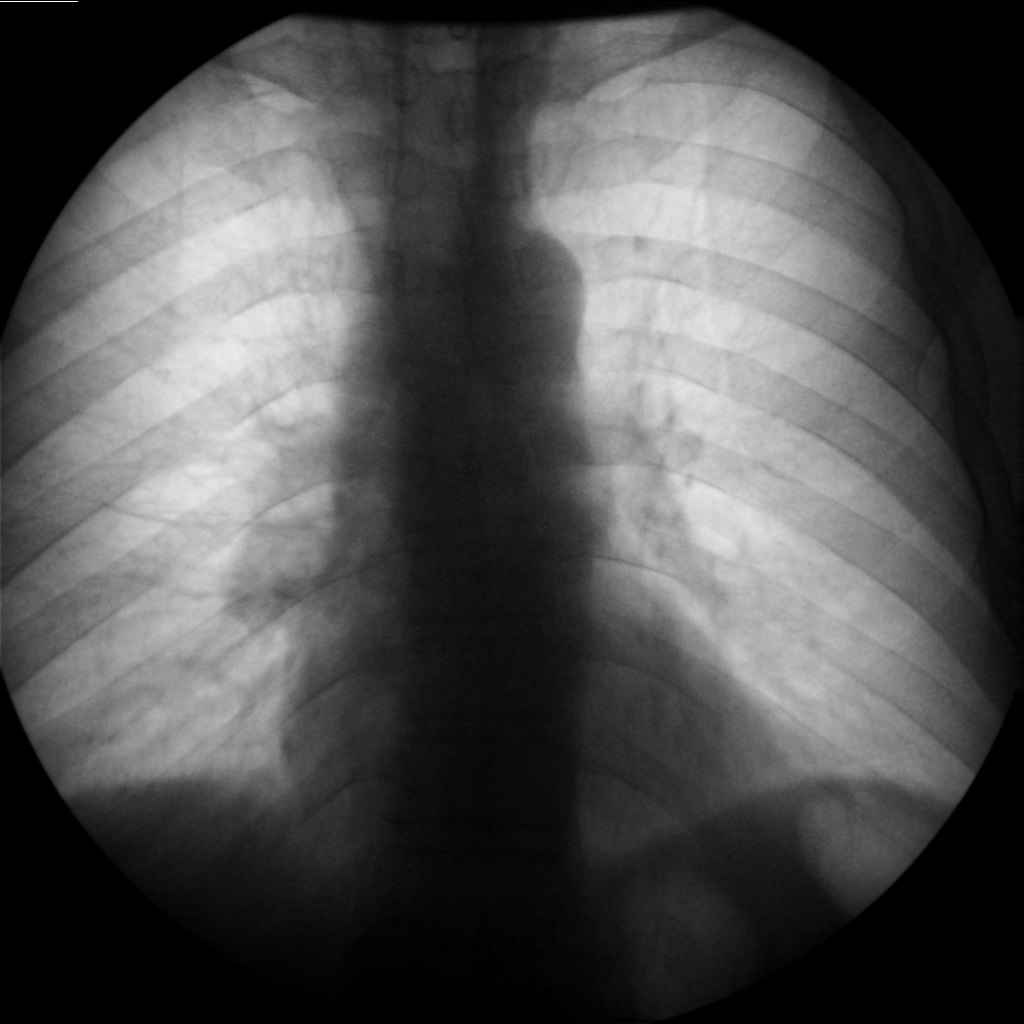

- გულმკერდის რენტგენოგრაფია რეზექციიდან 2 კვირის შემდეგ

მარცხენა ფილტვი მთლიანად გაშლილია